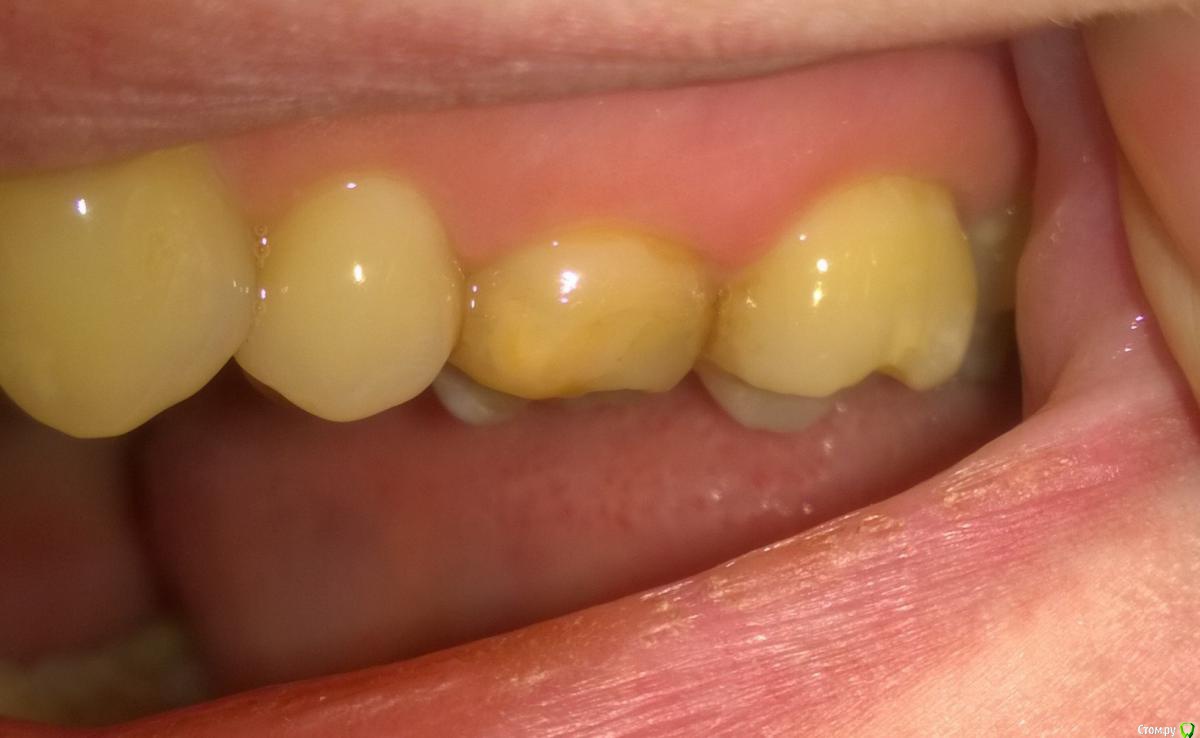

Fenya Опубликовано 12 апреля, 2016 Поделиться Опубликовано 12 апреля, 2016 Добрый вечер, уважаемые специалисты! Помогите пожалуйста определиться с планом лечения! Разболелся 6-ой верхний зуб, посетила две стоматологии - в первой однозначно сказали удалять и через месяца 4 задуматься об имплантации; во второй предложили три варианта на выбор: 1. удаление и постановка моста без удаления нервов зубов; 2. можно попробовать полечить, если очень хочется, но естественно гарантий вообще никаких; 3. ну и удаление с последующей операцией по восстановлению кости и имплантация. Врач сказал, что киста большая, если удалять зуб, то очень осторожно, т.к. здоровой кости очень мало и можно ее сломать (пишу на своем обывательском языке - как поняла, простите, если допускаю терминологические ошибки ). Врач предпочитает первый вариант развития событий, т.к. неблагоприятная ситуация для имплантации, а лечение может поможет, а может и нет... Ну и вопрос: Может попытаться полечить? Я же вроде ничего не теряю, кроме времени и денег, в случае неблагоприятного исхода? Или все-таки могу усугубить ситуацию со здоровьем пытаясь продлить жизнь зубу? Мостов патологически боюсь, собственно как и имплантов (установила на единичке имплант два месяца назад - до сих пор беспокоит, хотя по внешним признакам врач говорит все отлично, да и по отзывам других пациентов должна была о нем давно забыть). Ссылка на комментарий

Fenya Опубликовано 21 апреля, 2016 Автор Поделиться Опубликовано 21 апреля, 2016 Вы бы показали нам КТ и Все снимки которые есть, возможно мнение изменилось бы.По факту есть воспалительный процесс ( киста или нет это еще неизвестно) который затрагивает дно пазухи. И требуется устранение источника инфекции внутри зуба либо зуба целиком. Такие скрины подходят или выложить все КТ? Если все, то подскажите, какие файлы выложить в файлообменник? Ссылка на комментарий